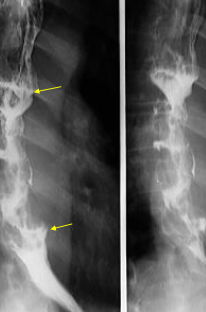

Neoplasm esofagian malign vegetant